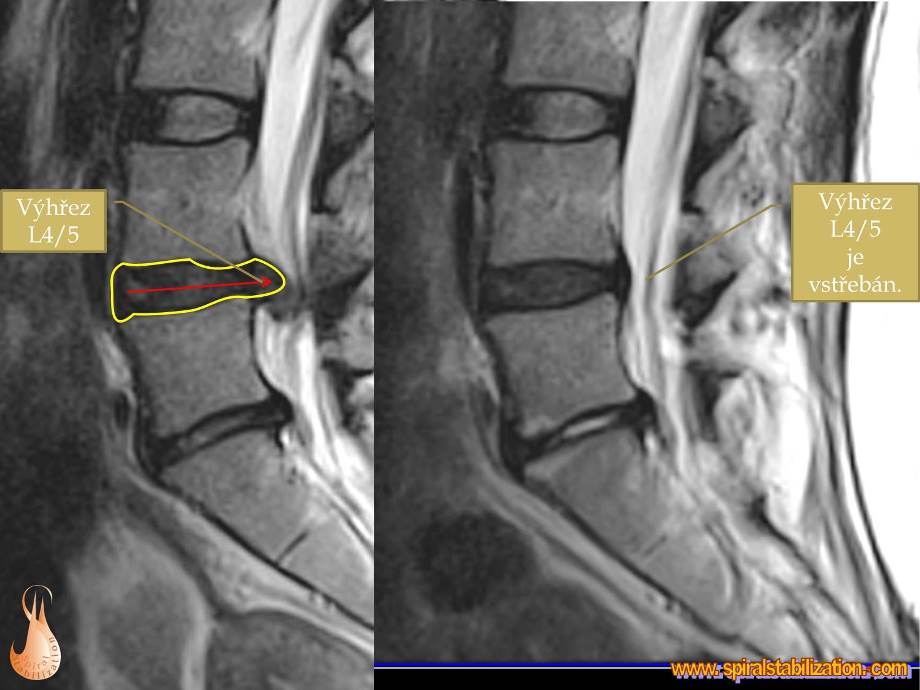

Vo väčšine prípadov dochádza k vyklenutiu platničky medzi 4. a 5. bedrovým stavcom (hernia disku L4/L5). V niektorých prípadoch môže dôjsť k vyklenutie medzi 5. bedrovým stavcom a 1. stavcom tvoriacim krížovú kosť (hernia disku L5/S1), čo sa prejavuje často poruchou citlivosti v oblasti vonkajšej strany stehna a predkolenia.

Vyklenutie hernie môže byť čiastočné, kedy je zachované spojenie s medzistavcovou platničkou, alebo úplné, kedy je toto spojenie prerušené a vytvára sa voľný sekvestor (sekvestor, z lat. Sequestro - dávam mimo, oddeľujem).

Výsledky hernia L4/L5